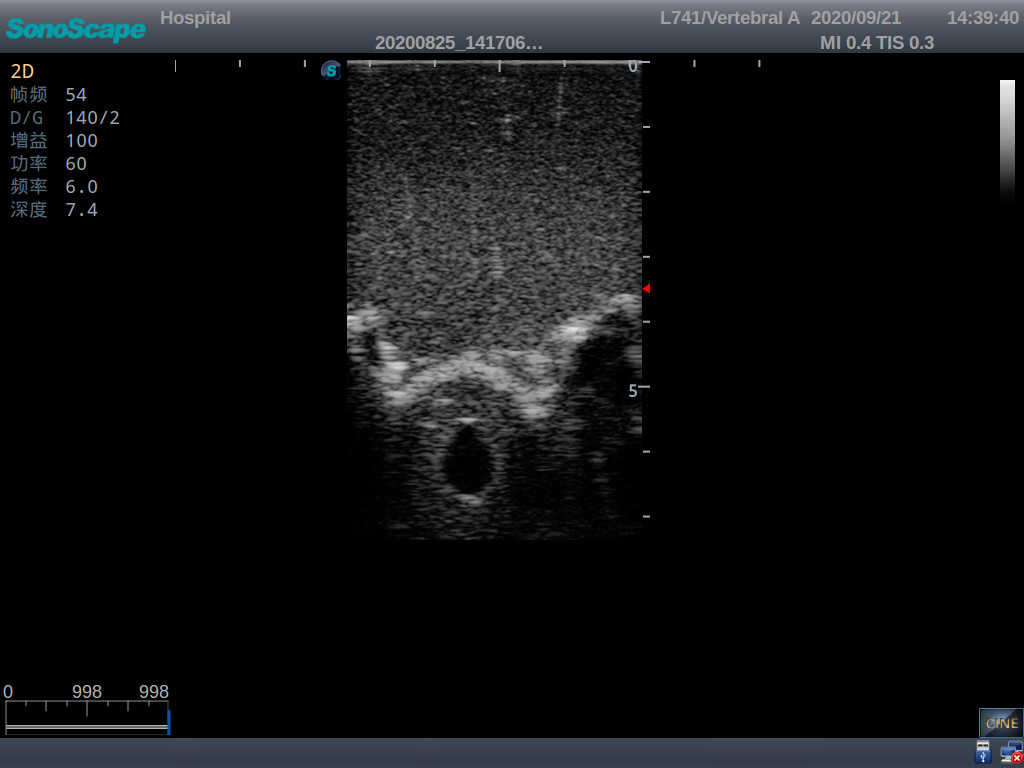

2) Real clinical ultrasound images

1) Ultrasound-guided lumbar puncture practice